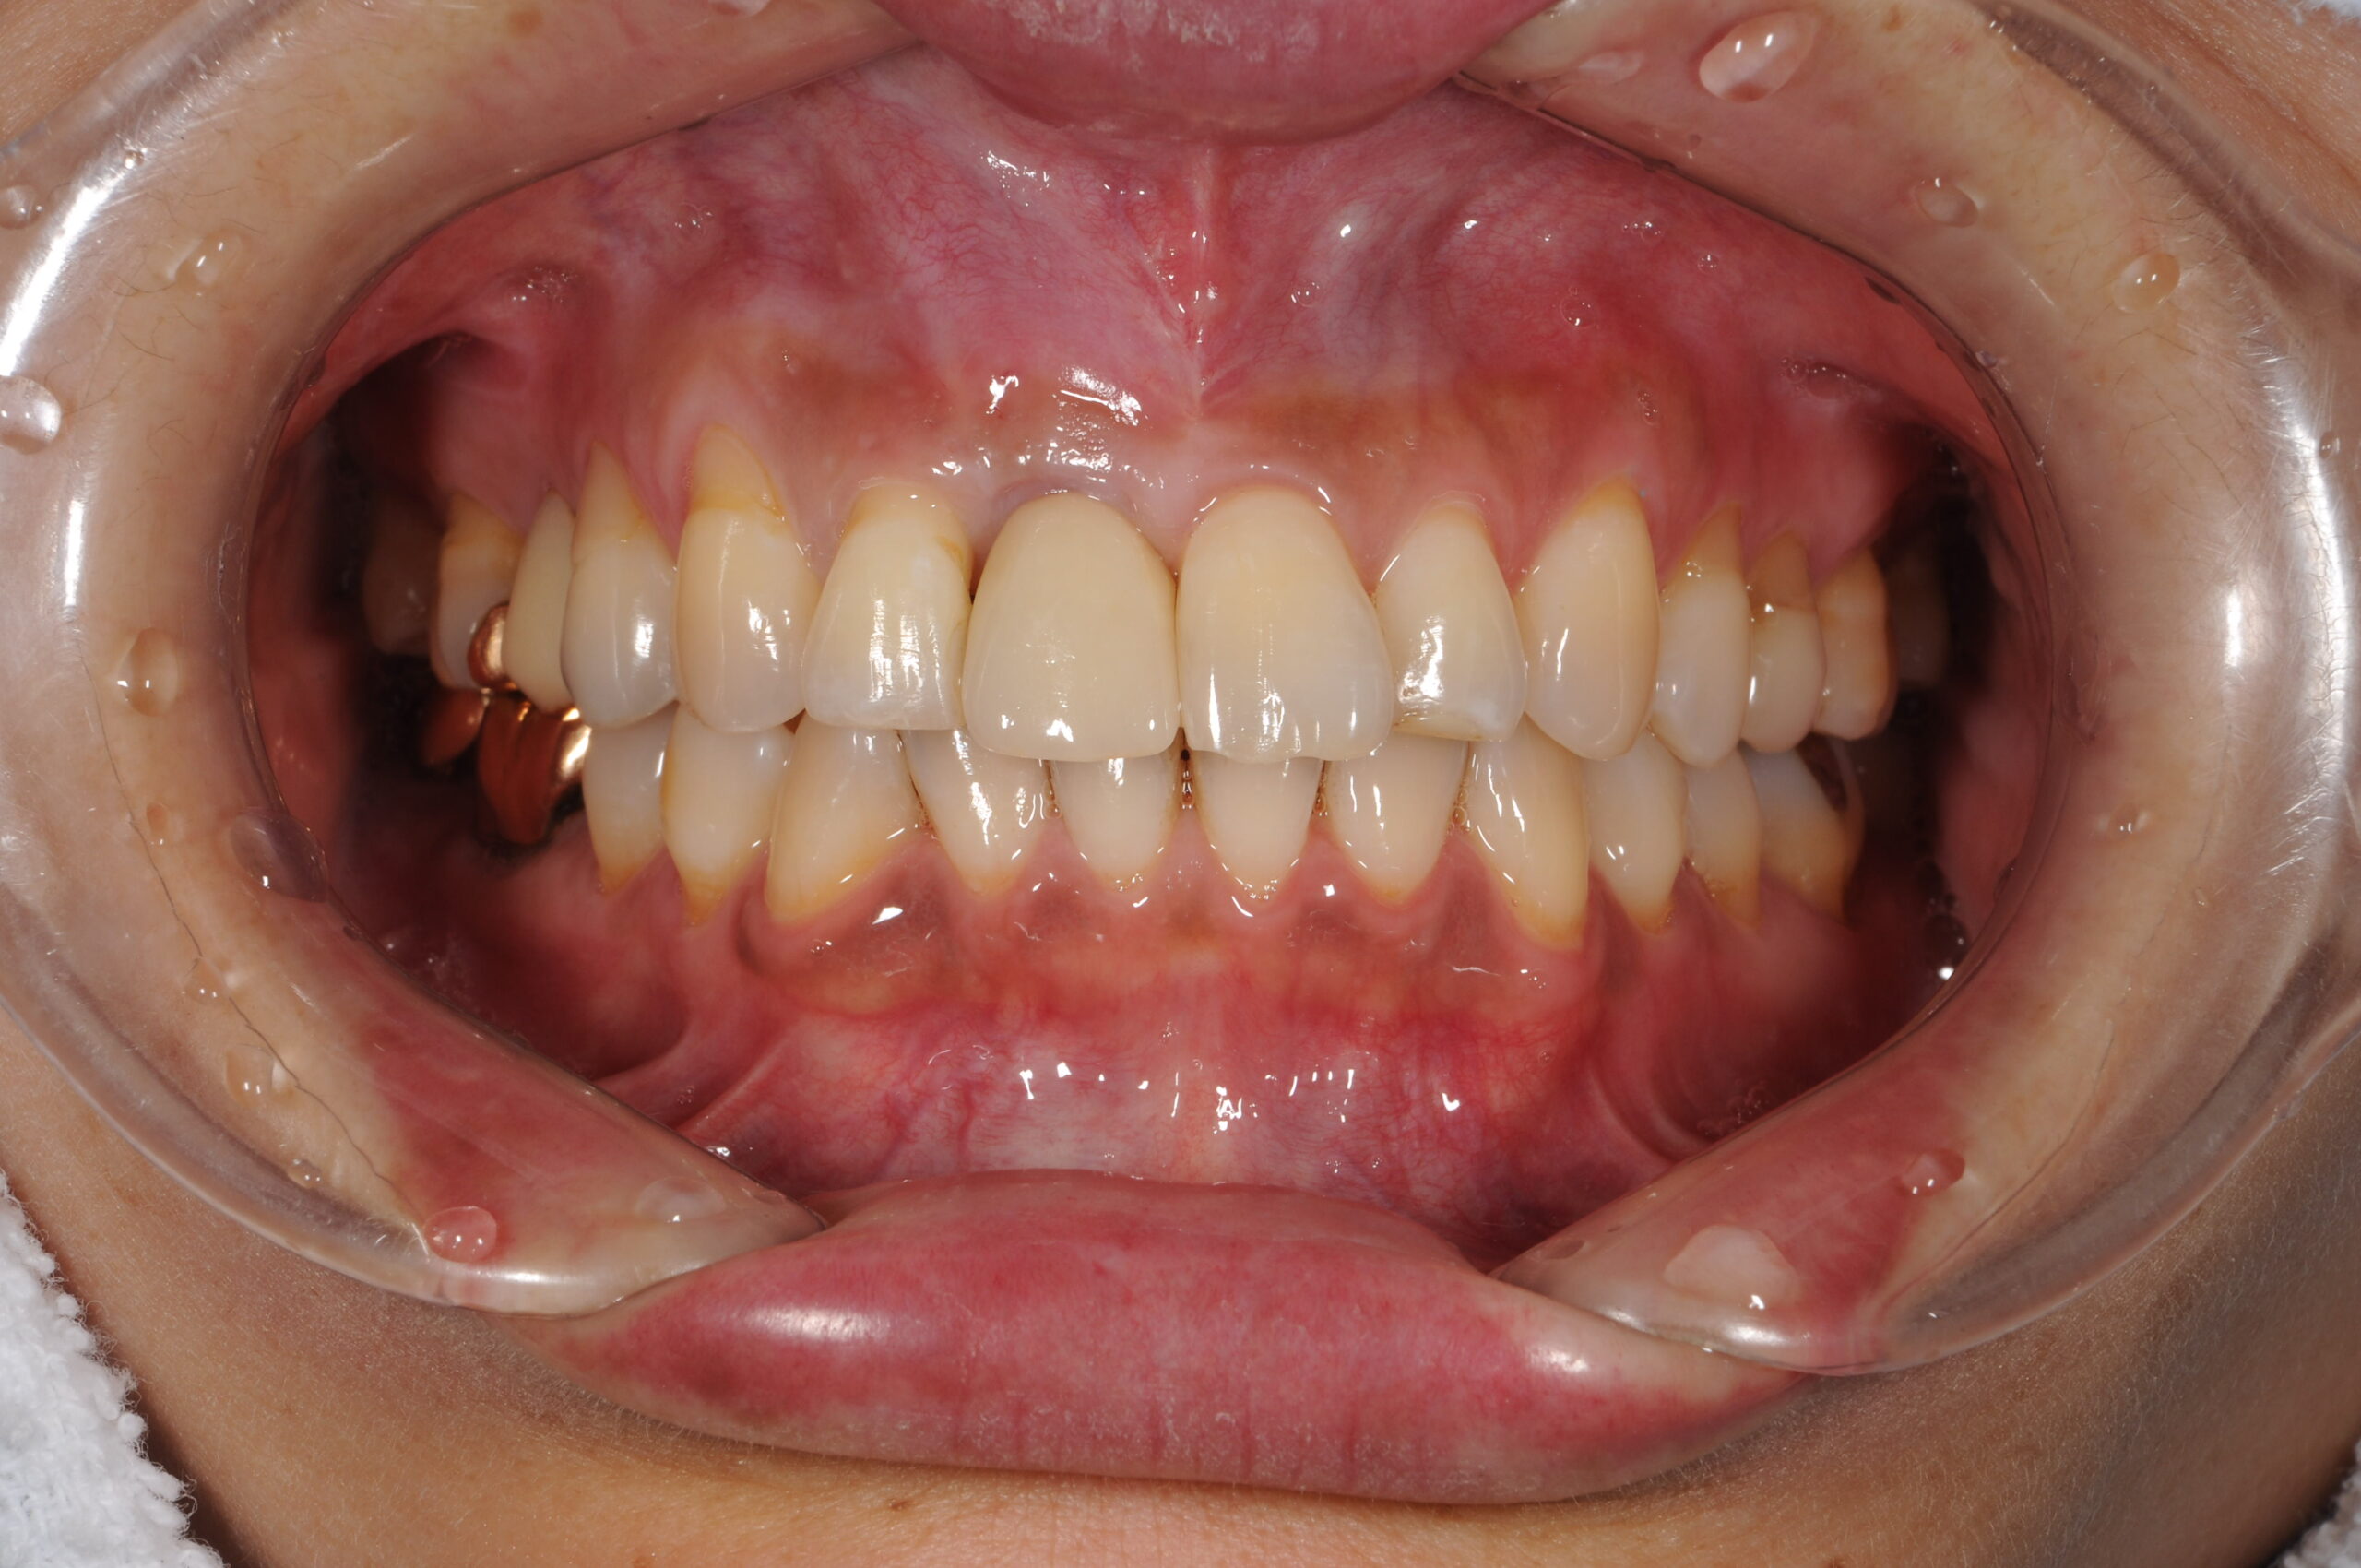

矯正治療とセラミックでの全顎治療の1例